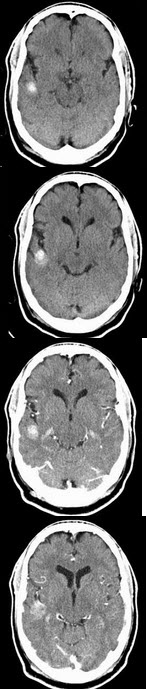

男,54岁,癫痫发作,请结合影像图像选择最可能的诊断( )

A:脑脓肿

B:脑出血

C:海绵状血管瘤

D:胶样囊肿

E:脑转移瘤